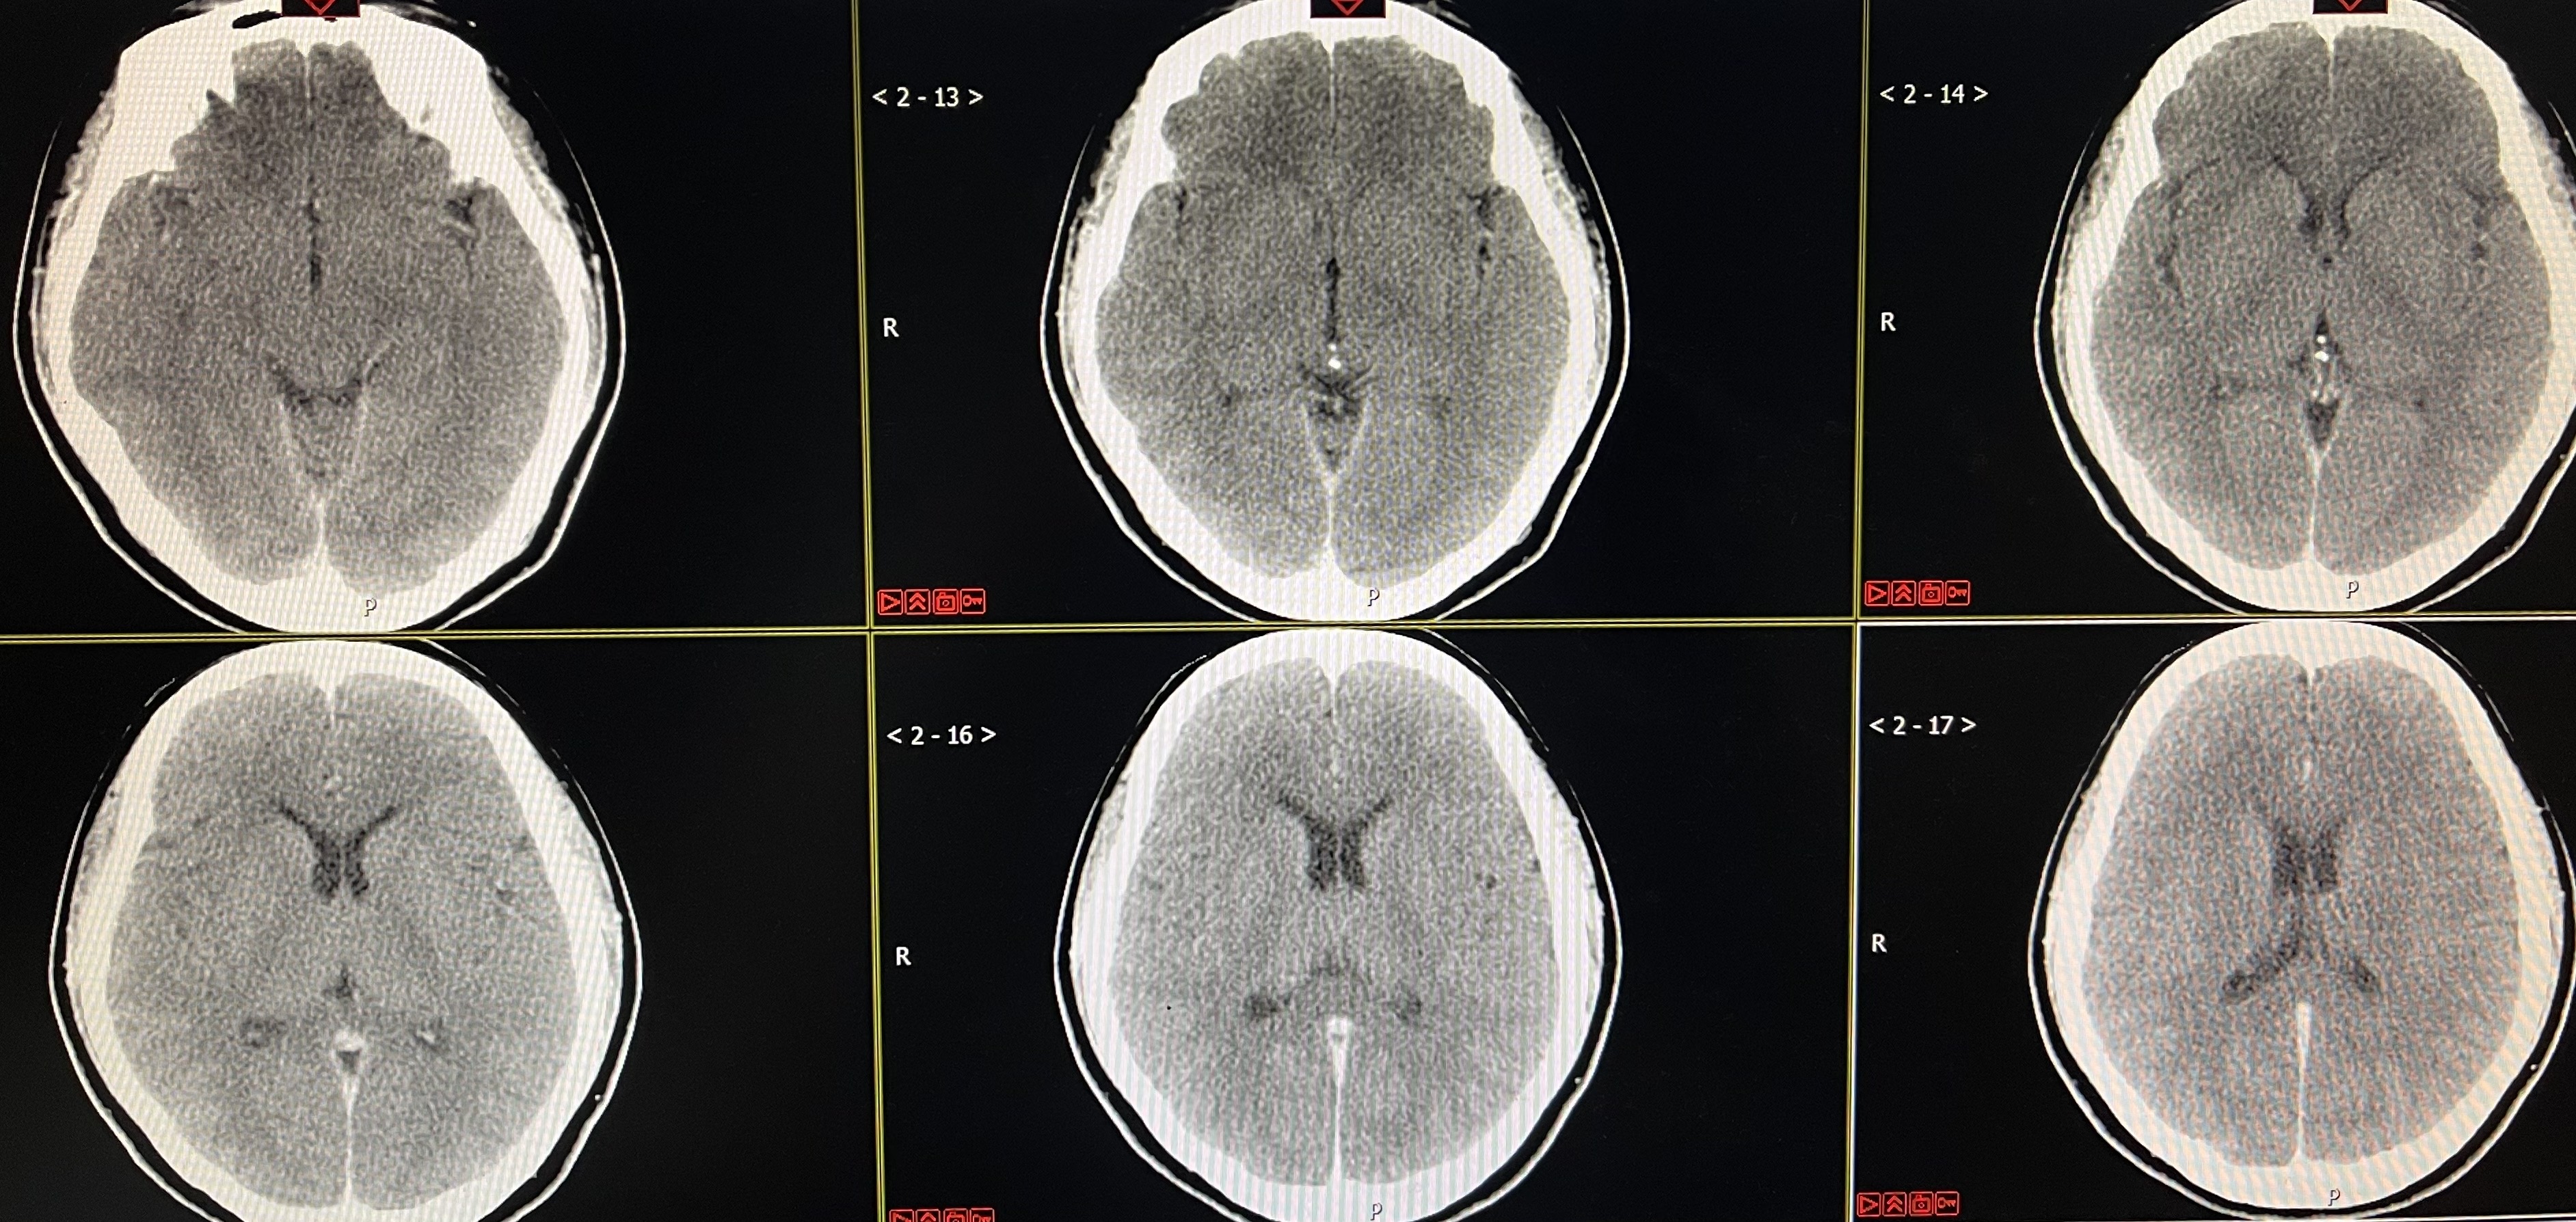

患者,女,33岁,因“头颈部疼痛伴恶心呕吐11周余”入院,有高血压病史六年余,最高时230/120mmhg。2020.10.09激动后出现头颈部疼痛,伴恶心呕吐,呕吐物为胃内容物,否认肢体乏力,否认两便失禁,否认意识不清,2020.10.12平湖市第一人民医院查头颅CT提示“左侧基底节区点状出血,脑室系统少量积血,蛛网膜下腔出血”,查头颅CTA提示“前交通动脉瘤”,经予以积极对症治疗,恢复尚可,头痛基本缓解。目前恢复尚可,现为进一步诊治收入病房。

术后即刻CT